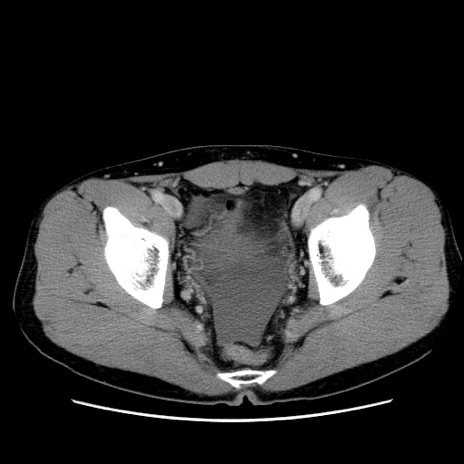

症例36(横断像)

【症例】20歳代 男性

【主訴】心窩部痛

【現病歴】今朝より上腹部痛あり。一旦軽快していたが再度出現したため救急要請。昨日夕に白身の魚を含む刺身を食べた。

【身体所見】BP 136/89mmHg、HR 74/min、BT 37.0℃、腹部:膨満、軟、心窩部に圧痛あり。反跳痛なし、筋性防御なし、腸雑音やや亢進あり。

【データ】WBC 17700、CRP 0.48